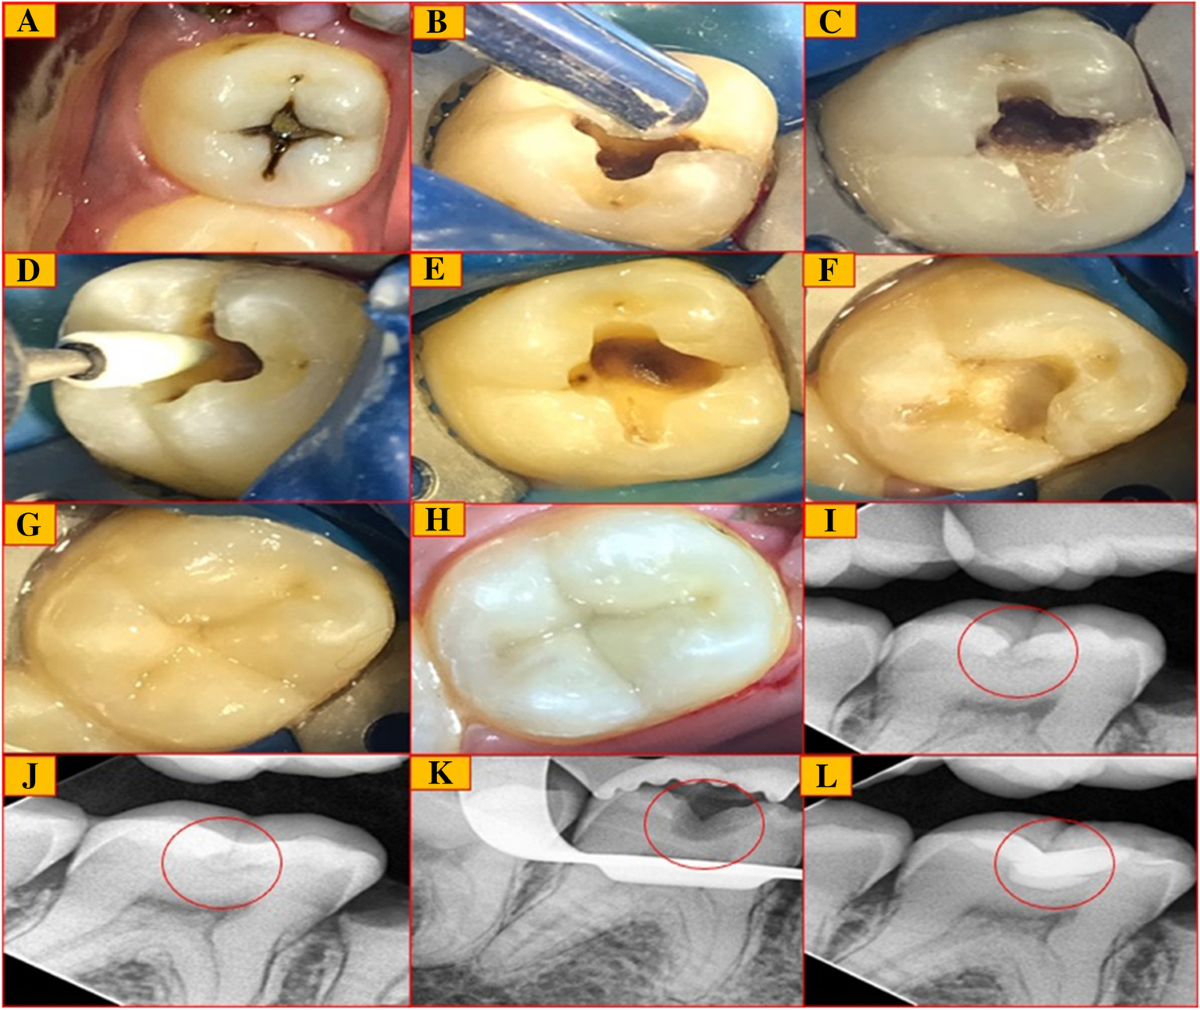

تشخیص پوسیدگی اوریس تک oristech

توضیحاتشناساگر پوسیدگی OrisTech، یک محلول تشخیص پوسیدگی است که در سه رنگ قرمز، سبز و آبی عرضه میگردد.احتمال عدم تشخیص پوسیدگی توسط دندانپزشکان در حین درمان وجود دارد. این محصول به برداشت لایه عاج پوسیده و عفونى شده خارجى کمک مـى کند و امکان حذف بهینه پوسیدگى را فراهم مى کند. همچنین از حذف عاج سالم و عاج با قابلیت مینرال شدن (Remineralizable) جلوگیری مـى کند که این اقدام باعث محافظت عاج ، پالپ و در نتیجه منجر به عدم حساسیت و حفظ ساختار سالم دندان مى شود. عاج پوسیده از دو لایه تشکیل شده است. لایه بیرونى(Outer Carious Dentin) دکلسیفاى شده و آغشته بـه باکترى است. این لایه قابل رمینرالیزاسیون نیست و باید برداشته شود.در عین حال، لایه داخلى (Inner Carious Dentin) فقط تا حدى دکلسیفاى شده و عفونى نشده است. این لایه هنوز قابل معدنی شدن مجدد است و باید تا حد امکان حفظ شود. شناساگر پوسیدگى کمک بسیار خوبى به دانشجویان دندانپزشکى در درمان محافظه کارانه می کند.